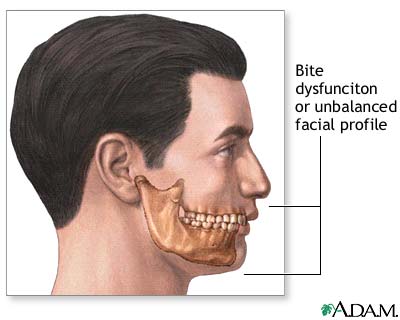

Surgery to correct bite problems (orthognathic surgery) can be done at the same time as chin surgery.

Chin augmentation is mostly done to balance the appearance of the face by making the chin longer or bigger compared to the nose. The best candidates for chin augmentation are people with small or receding chins (microgenia), but who have a normal bite.